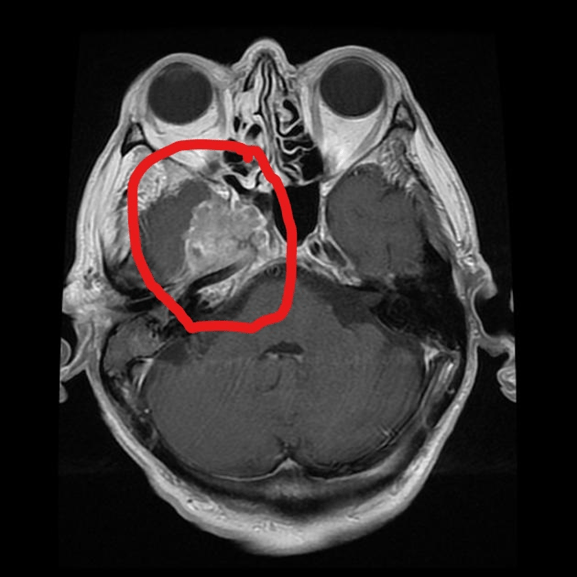

It is a scan that combines radio and magnetic waves to visualize the internal organ with detailed images. Common reasons to use the MRI scan are to determine whether the lump is cancerous, the size of the cancer, and whether it has metastasized (spread) post-surgery or when radiotherapy is required (Pulamati et al., 2023). An MRI scan of the brain tumour is in Figure 8. Other tumours used to diagnose via conventional MRI are prostate, primary bone, soft tissue sarcomas, bladder, spinal cord, and ovarian cancers (Pulamati et al., 2023). It can provide information on soft tissues that a CT scan cannot do. For example, the brain and spinal cord: strokes, nerve damage, and multiple sclerosis. Sports injuries in the muscles, tendons, ligaments, and joints. The abdomen and pelvis are seen more clearly, particularly the kidneys, prostate, liver, uterus, and ovaries. The structure and function of the heart are also assessed.

Figure 8: MRI scan of the brain. The tumour is marked with a red outline in an axial plane